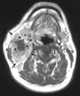

Necrotic lymphadenopathy

Lymphadenopathy or adenopathy is a disease of the lymph nodes, in which they are abnormal in size or consistency. Lymphadenopathy of an inflammatory type (the most common type) is lymphadenitis, producing swollen or enlarged lymph nodes. [Source: Wikipedia ]